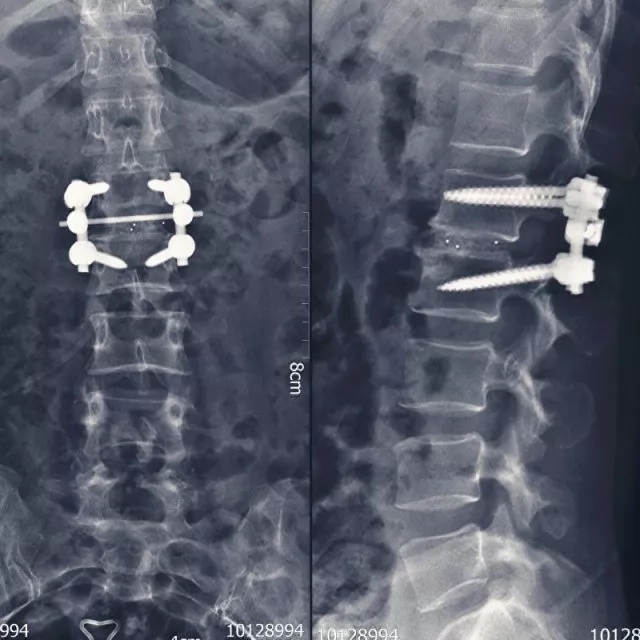

? 術(shù)后內(nèi)固定狀態(tài)

術(shù)后,患者劇痛很快消失,在植入式生物激光脊神經(jīng)治療儀的治療下神經(jīng)功能較快恢復(fù),7月2日,術(shù)后7天出院時(shí),患者雙下肢髂腰肌肌力由術(shù)前II級(jí)恢復(fù)到IV+級(jí),雙側(cè)股四頭肌力由III級(jí)恢復(fù)到V級(jí),可以正常行走,大小便恢復(fù)正常。